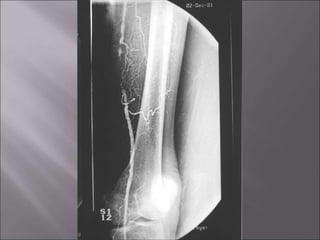

Observe

*Affection

from distal to

proximal.

*Pruning of

tibial vessels

and foot arch.

Clinical features: 1.Usually Youngmale 2. Heavy smoker 3. Migratory thrombophlebitis 4. ± Raynaud’s phenomenon

• 86.

• 88.